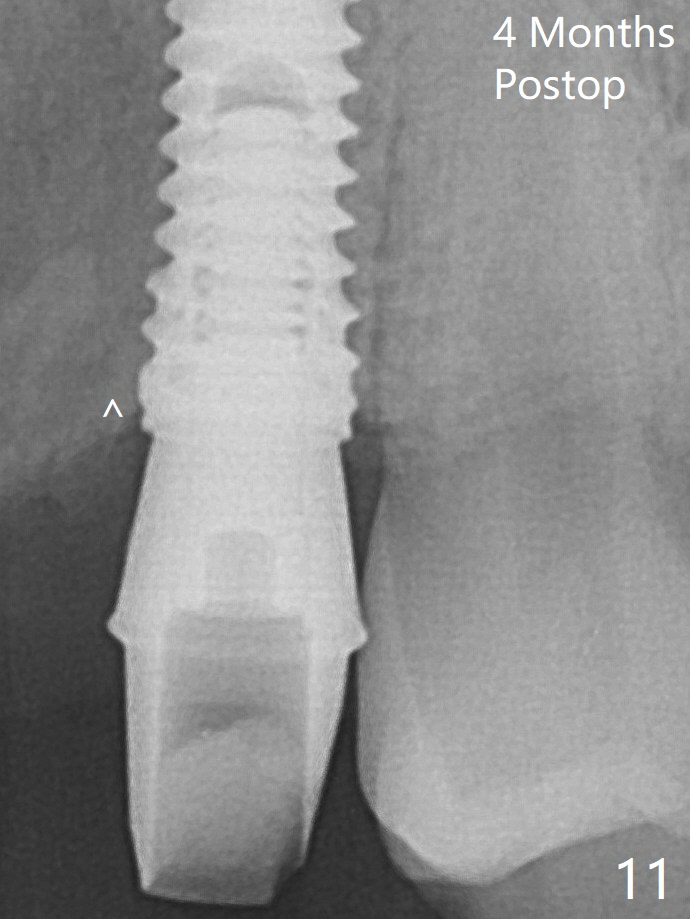

术后4个月牙槽嵴(图八:*)吸收(图十一:^),刚植入时的间隙(图八:>)四个月后仿佛消失。